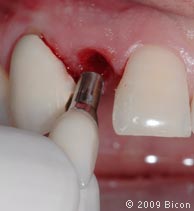

21. Установка направляющих штифтов 3,0 мм внутрь имплантатов.

22. Установка в имплантат обрезанной пластиковой заглушки.

23. Закрытие имплантата собранной костной тканью.